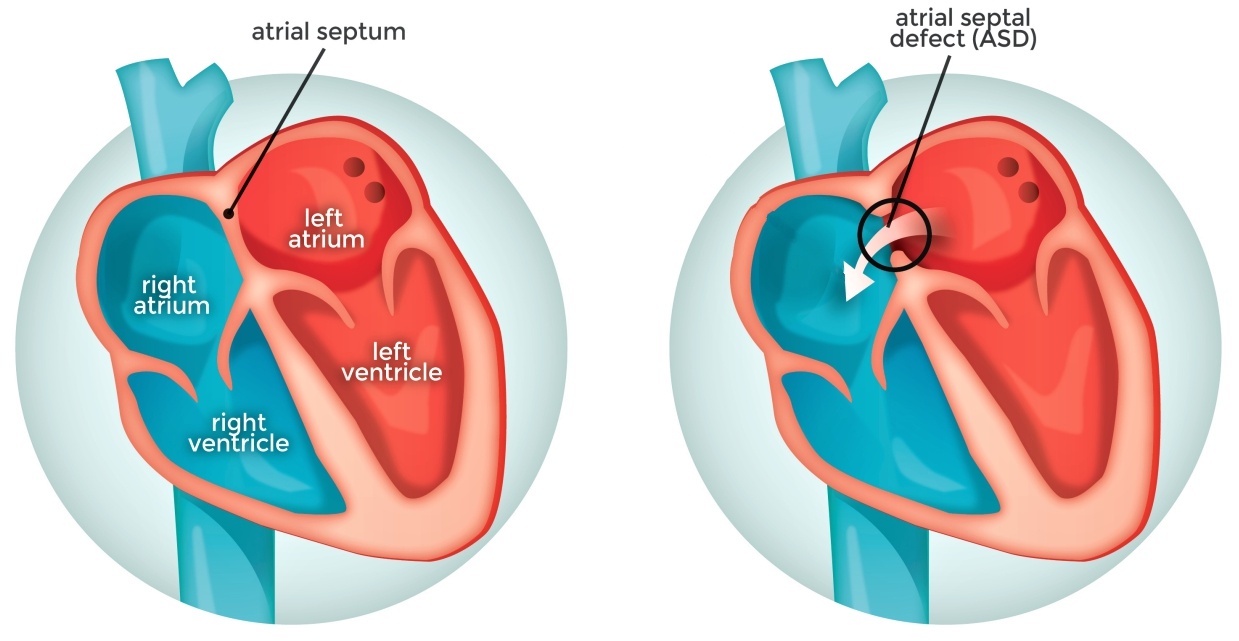

– Trong quá trình phát triển của thai, vách liên nhĩ phát triển để phân chia nhĩ trái và phải. Tuy nhiên, một lỗ ở vách được gọi là lỗ bầu dục cho phép máu từ nhĩ phải qua nhĩ trái trong quá trình phát triển của thai. Lỗ thông này cho phép máu không đi qua phổi thai không có chức năng, trong khi thai vẫn nhận oxy từ nhau. Một lớp mô được gọi là vách nguyên phát hoạt động như một van tại lỗ bầu dục trong quá trình phát triển thai. Sau khi sinh áp lực bên phải của tim giảm khi phổi mở và bắt đầu hoạt động, làm cho lỗ bầu dục đóng hoàn toàn.

– Khoảng 25% ở người trưởng thành lỗ bầu dục này không đóng hoàn toàn. Trong những trường hợp này, bất kỳ một sự tăng áp lực trong hệ tuần hoàn phổi (do tăng áp phổi, tạm thời trong khi ho) có thể làm lỗ bầu dục vẫn còn mở. Trường hợp này được gọi là tồn tại lỗ bầu dục, một loại thông liên nhĩ.

– Thông liên nhĩ là bệnh lý tim bẩm sinh chiếm từ 7-15% và xếp hàng thứ 5 trong các bệnh lý tim bẩm sinh nói chung, bệnh chủ yếu gặp ở nữ giới.

+ Thông liên nhĩ lỗ tiên phát (ASD-op): có thể xảy ra đơn độc nhưng thông thường xảy ra trong bệnh cảnh tim bẩm sinh phức tạp (kênh nhĩ thất), vị trí nằm thấp, sát van nhĩ thất.

+ Thông liên nhĩ lỗ thứ phát (ASD-os): Đây là tình trạng thường gặp nhất, chiếm đến 70% các trường hợp, có thể xảy ra đơn độc và vị trí nằm ở trung tâm của vách liên nhĩ. Lỗ thông liên nhĩ thứ phát thường có kích thước từ 10-30 mm.

+ Thông liên nhĩ xoang tĩnh mạch (ASD-sv): Đây là một tình trạng hiếm gặp và có 2 loại: Loại tĩnh mạch chủ trên: nằm ngay dưới lỗ đổ của tĩnh mạch chủ trên vào nhĩ phải. Thông liên nhĩ xoang tĩnh mạch chủ trên thường đi kèm với hồi lưu tĩnh mạch phổi bất thường / Loại tĩnh mạch chủ dưới thì nằm sát lỗ đổ vào của tĩnh mạch chủ dưới vào nhĩ phải.

+ Thông liên nhĩ xoang vành (ASD-cs): do mất trần xoang vành, trường hợp này vô cùng hiếm gặp.

– Khoảng 15% các trường hợp bóng tim bình thường.

– Luồng thông trái => phải: bóng tim to do giãn nhĩ phải và thất phải, mỏm tim chếch lên. Nhĩ trái và thất trái bình thường.

– Động mạch chủ bình thường hoặc nhỏ hơn do giảm cung lượng tim.

– Cung động mạch phổi giãn do tăng cung lượng => tăng lưu lượng tuần hoàn phổi chủ động.

– Khi tăng áp lực động mạch phổi nặng => đảo chiều luồng thông => động mạch phổi giãn ở trung tâm và co nhỏ ở ngoại vi => phế trường ngoại vi sáng hơn bình thường.